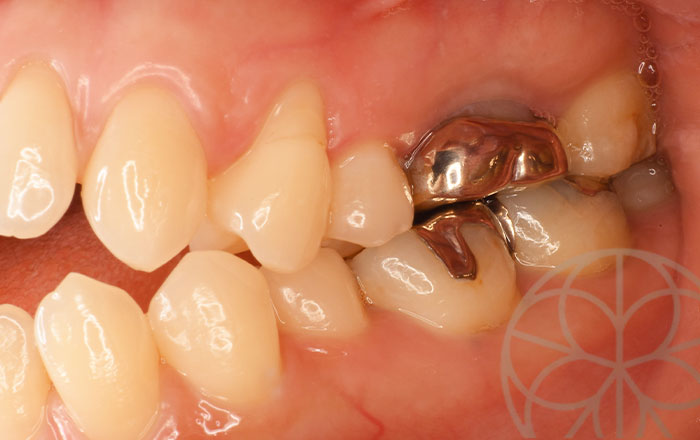

治療状況③

感染根管治療

まずは、銀歯を外します。写真は銀歯を外したところです。黄色矢印のところで、虫歯再発しており、ここから細菌が入っていったのではないかと思います。